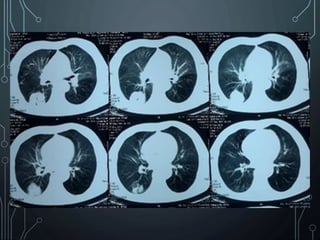

CT SCAN TORAKS

• Nodul tepi

ireguler,

spiculated

• Golden S sign

• Air

bronchogram

sign

• Penyangatan

20HU atau

lebih